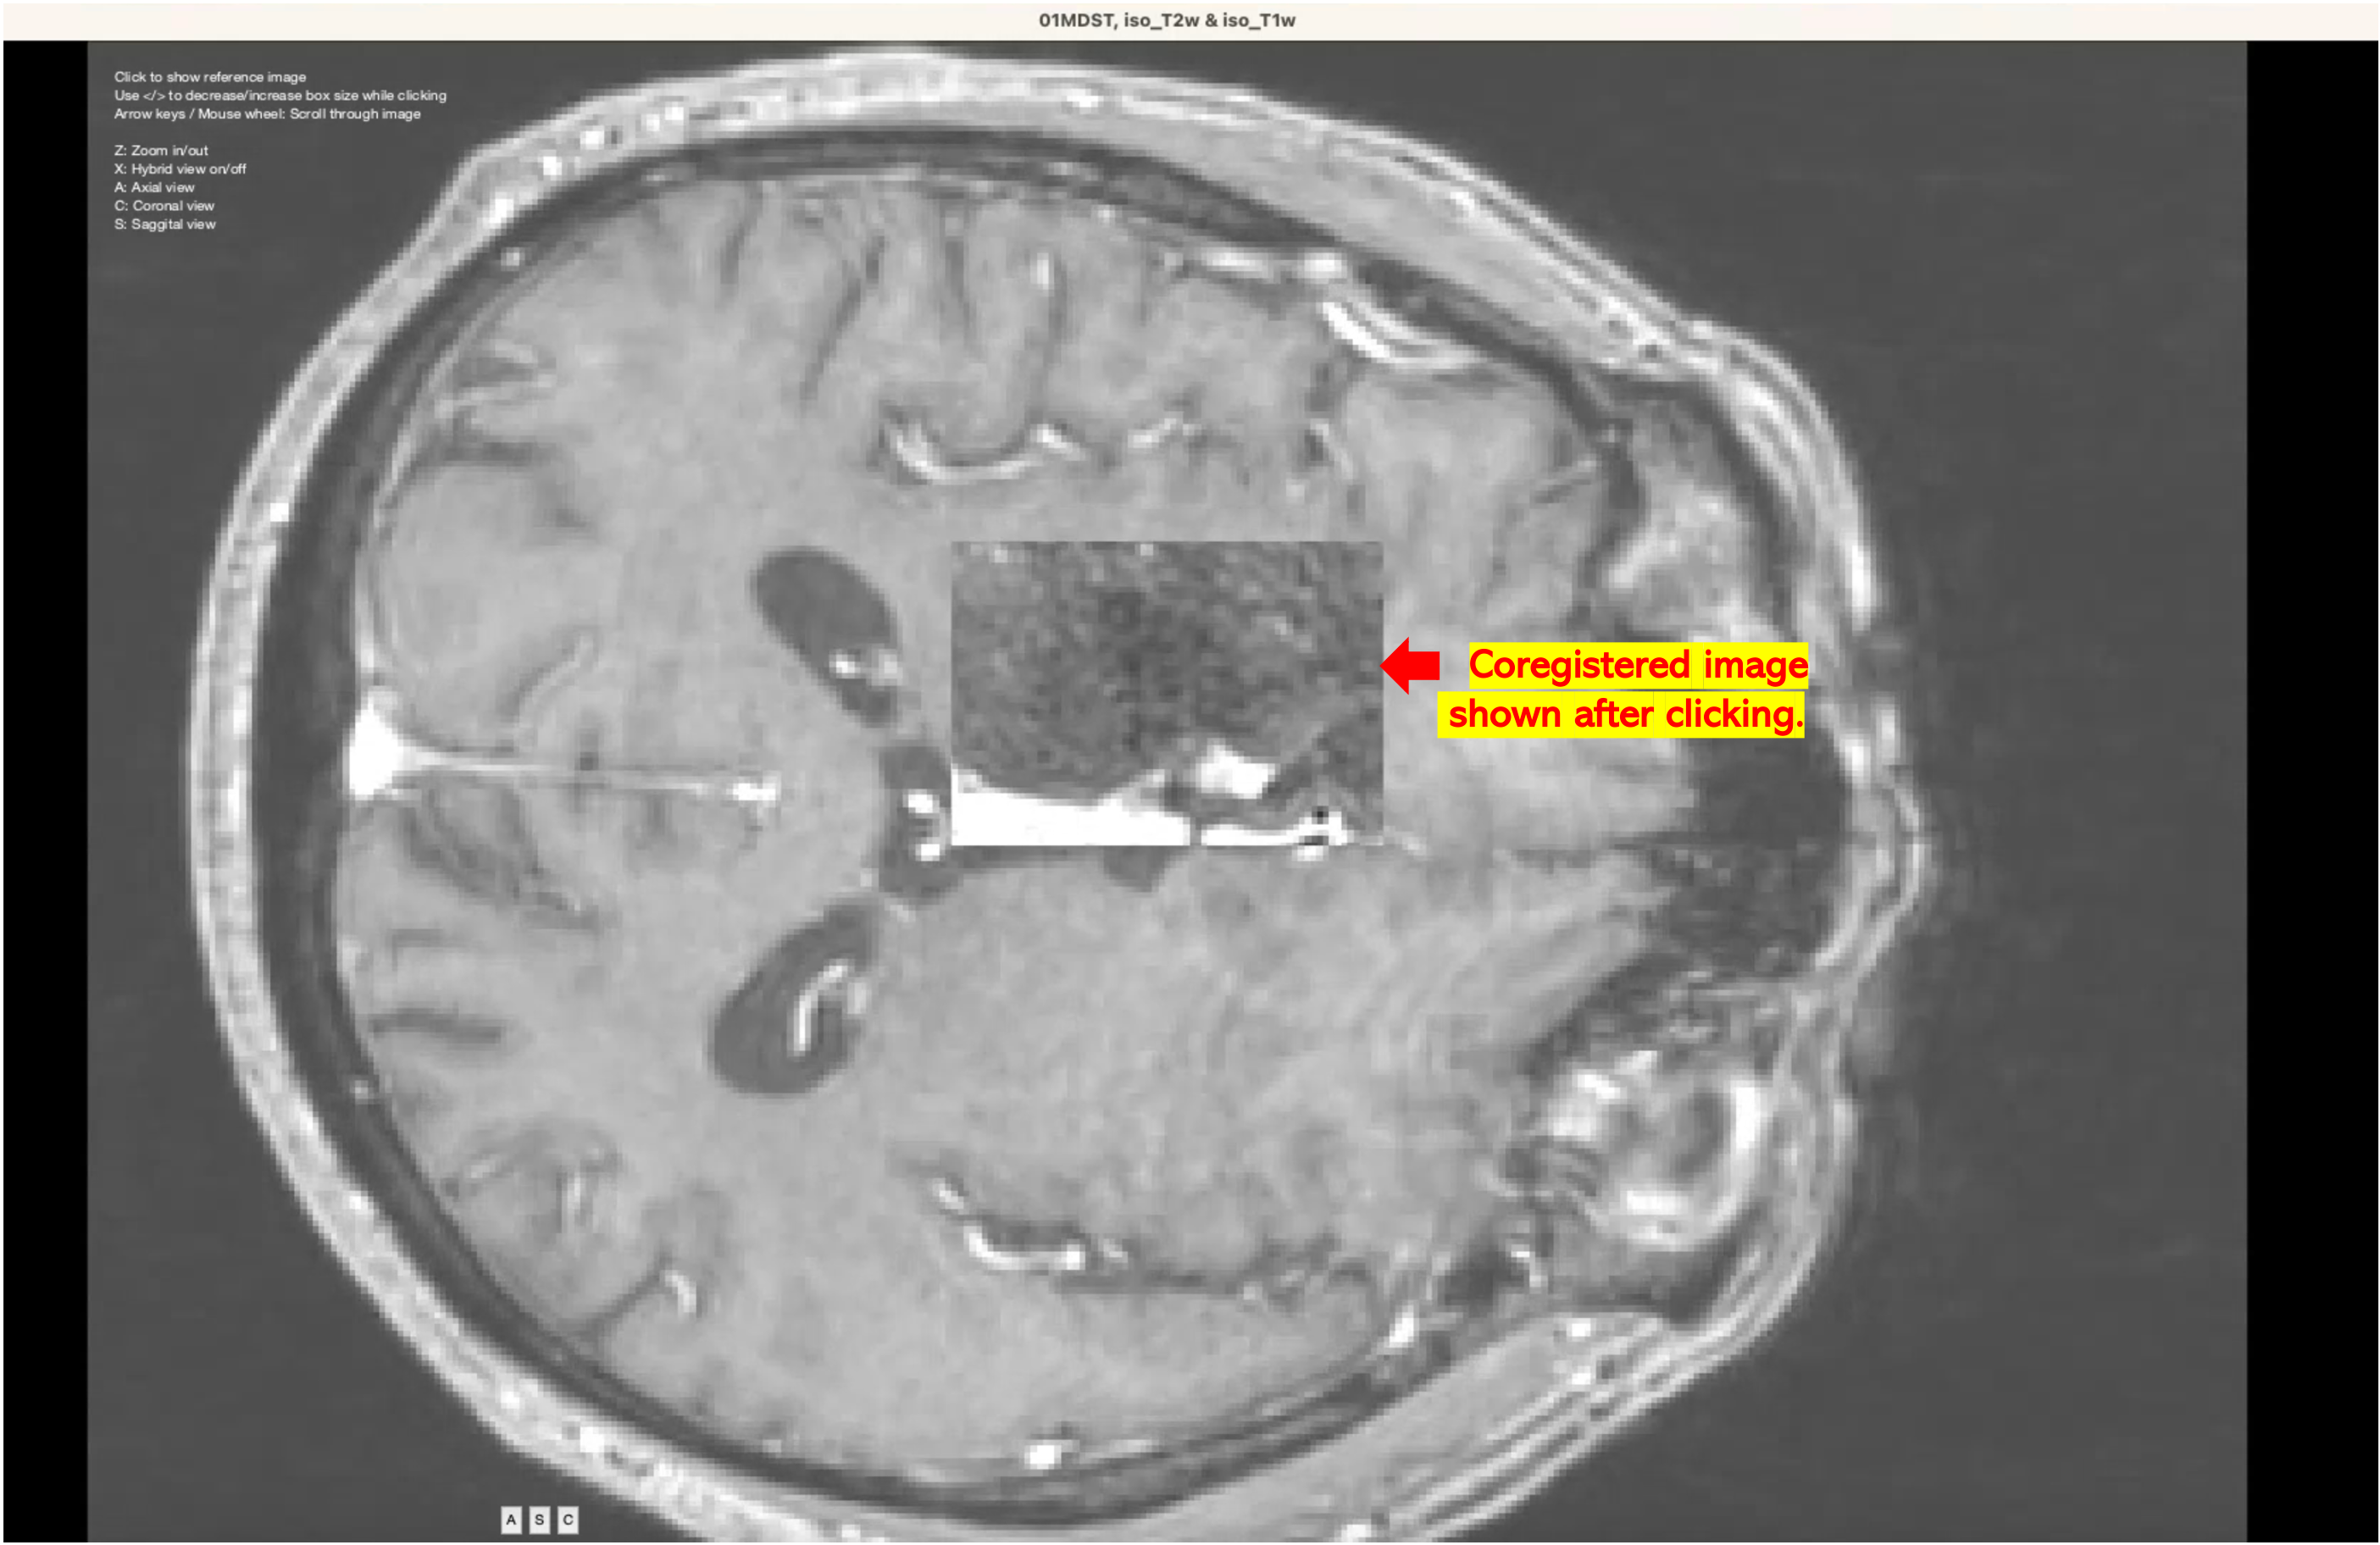

Image 1: Window with coregistration results.

Image 1: Window with coregistration results.